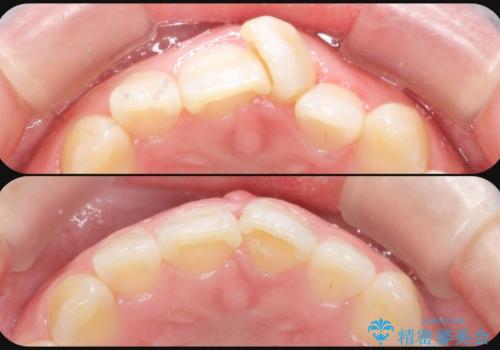

[ マウスピース矯正 ] 出っ歯に見える前歯を改善したい

- 「出っ歯に見える前歯を改善したい。」と矯正治療を希望され来院されました。

・2級性の咬合関係(上顎前突) ・前歯の傾斜

を改善すべく、マイクロインプラントを用いた奥歯の後方移動を行い上記の問題を解決していきます。

マイクロインプラントを用いてしっかりと後方移動を行ったことで、奥歯の咬合関係・前歯の傾斜をしっかりと改善し、機能的・審美的に大きく改善する矯正治療を行うことができました。